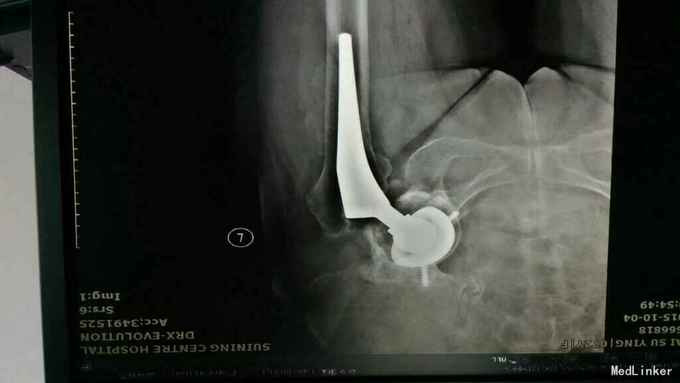

主诉:左髋关节置换术后疼痛活动受限3年 病史:3年前患者因左股骨颈骨折在当地县医院就诊,诊断明确后行全髋关节置换术,术前正常出院。出院后即感左髋关节疼痛不适,活动疼痛加重,休息缓解,疼痛位于腹股沟明显。反复于当地医院及成都等医院就诊,诊断不明确,考虑有金属过敏可能。4天前患者疼痛加重,活动进一步受限,无关节红肿,无肿胀,无畏寒发热,无其他关节疼痛。为进一步治疗收入我科。 患病以来。精神食欲可,体力下降。

查体:轮椅推入,左髋关节后外侧见10cm手术切口瘢痕,双侧腹股沟压痛,双侧大转子叩痛,双髋关节活动受限,4字实验(+),双下肢肌力3级。左乱关节屈曲90度,旋转不能。左下肢纵向叩痛(+)。 辅助检查:彩超示脂肪肝。x线腰椎骨质疏松,压缩性骨折。ESR 38,CRP 12。 影像学如下:

诊断:左髋关节置换术后假体松动; 右侧股骨头缺血坏死; 重度骨质疏松症 高血压病 压缩性骨折 治疗:左髋关节翻修术。(植骨、钛网骨水泥杯,骨水泥柄或翻修长柄MP(Link))